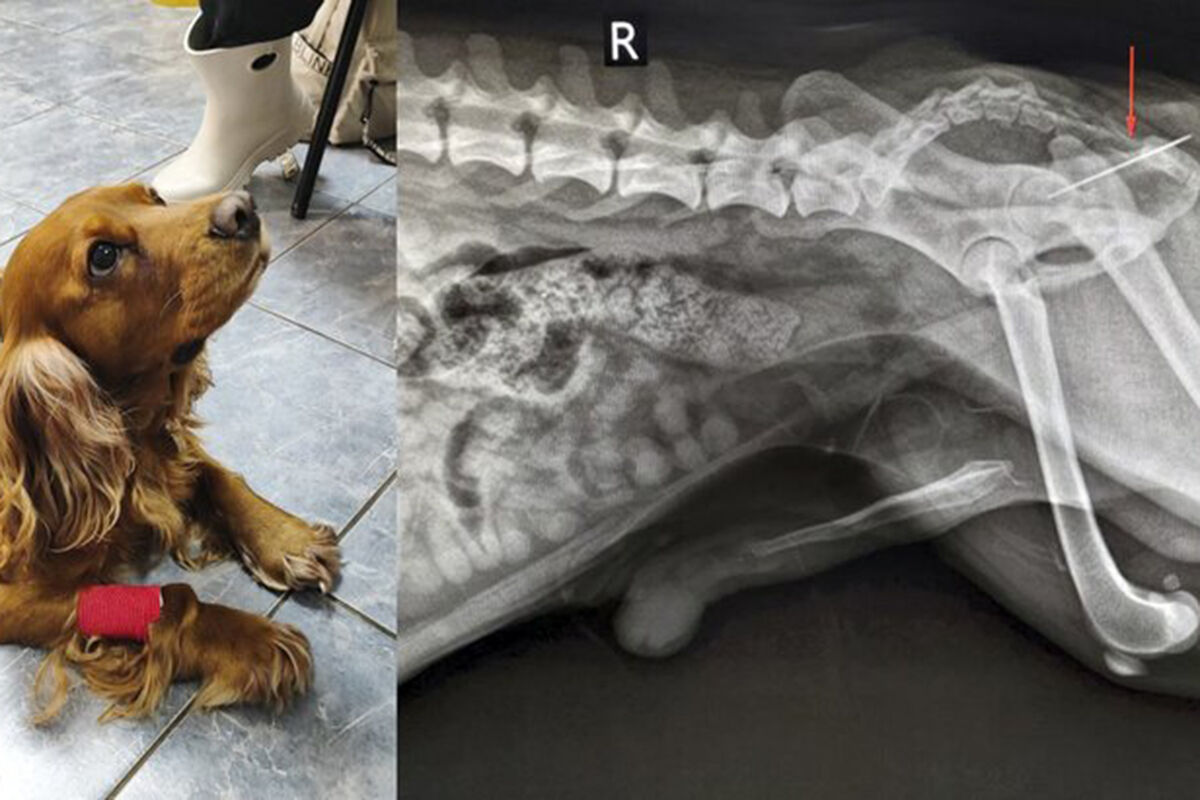

"При осмотре терапевт Анна Кубатина заметила, что из заднего прохода Вольта торчит швейная нитка. Пациента срочно отправили на рентген", – добавили в пресс-службе.

Врачи установили, что за ниткой тянулась и игла, которая застряла в прямой кишке. Хирург Евгений Бахтин и анестезиолог Светлана Дорожкина провели операцию по извлечению иглы, после этого питомца отпустили домой.